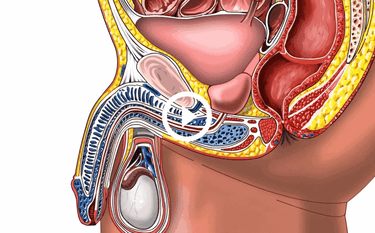

IMPOTENCE

Incurable sexual impotence

PROSTATE ADENOMAS

The proliferation of prostate tissue, formation of tumors, and "ganglia"

ONCOLOGY

Malignant tumor, the most common cause of death in men